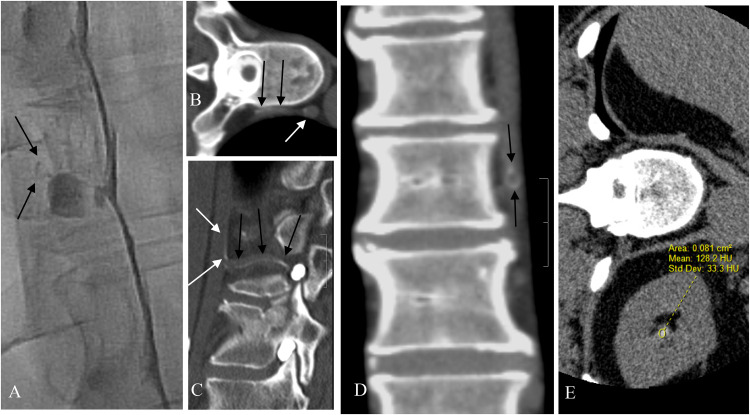

目的本文介绍了一种顺序侧卧数字减影脊髓造影(LDDSM)与侧卧CT (LDCT)密切配合的策略,以促进脑脊液(CSF)-静脉瘘(CVF)定位。材料与方法回顾性分析来我院评估脑脊液泄漏的患者。排除1型和2型渗漏患者,以及未出现颅内低血压的MR脑污点的患者。所有患者均连续行ldddsm和LDCT。如果CVF未定位在第一对ldsm - ldct上,则患者返回进行对侧检查。检查CVF和肾盂内造影剂积累的图像,以Hounsfield单位(HU)的肾盂造影剂评分(rpc)表示。结果本组共纳入22例患者。22例患者中有21例(95%)被确定为CVF,与CVF同侧的ldsm - ldct对的RPCS范围为71至423,平均为146 HU。8例患者在CVF对侧的LDDSM-LDCT对阴性侧的RPCS,平均为51 HU。在4例患者中,最初的双侧LDDSM- ldct对未显示CVF的位置,但在这4例中,有3例在第三个LDDSM上显示了CVF,重复到较高RPCS的同侧。结论序贯LDDSM-LDCT结合造影剂肾脏积聚评价策略可提高CVF的定位率,值得进一步评价。

PurposePresented here is a strategy of sequential lateral decubitus digital subtraction myelography (LDDSM) followed closely by lateral decubitus CT (LDCT) to facilitate cerebrospinal fluid (CSF)-venous fistula (CVF) localization.Materials and MethodsThis is a retrospective analysis of patients referred to our institution for evaluation of CSF leak. Patients with Type 1 and Type 2 leaks, and those not displaying MR brain stigmata of intracranial hypotension were excluded. All patients underwent consecutive LDDSM and LDCT. If the CVF was not localized on the first LDDSM-LDCT pair the patient returned for contralateral examinations. Images were reviewed for CVF and for accumulation of contrast within the renal pelvises expressed as a renal pelvis contrast score (RPCS) in Hounsfield units (HU).ResultsTwenty-two patients were included in this study. In 21 of 22 patients (95%) a CVF was identified yielding an RPCS for the LDDSM-LDCT pair ipsilateral to the CVF ranging from 71 to 423 with an average of 146 HU. An RPCS of the negative side LDDSM-LDCT pair contralateral to a CVF was available in 8 patients and averaged 51 HU. In 4 patients the initial bilateral LDDSM-LDCT pairs did not reveal the location of the CVF however in 3 of these 4 cases the CVF was revealed on a third LDDSM repeated ipsilateral to the higher RPCS.ConclusionThe strategy of sequential LDDSM-LDCT coupled with evaluation of renal accumulation of contrast agent appears to improve the rate of CVF localization and warrants further evaluation.